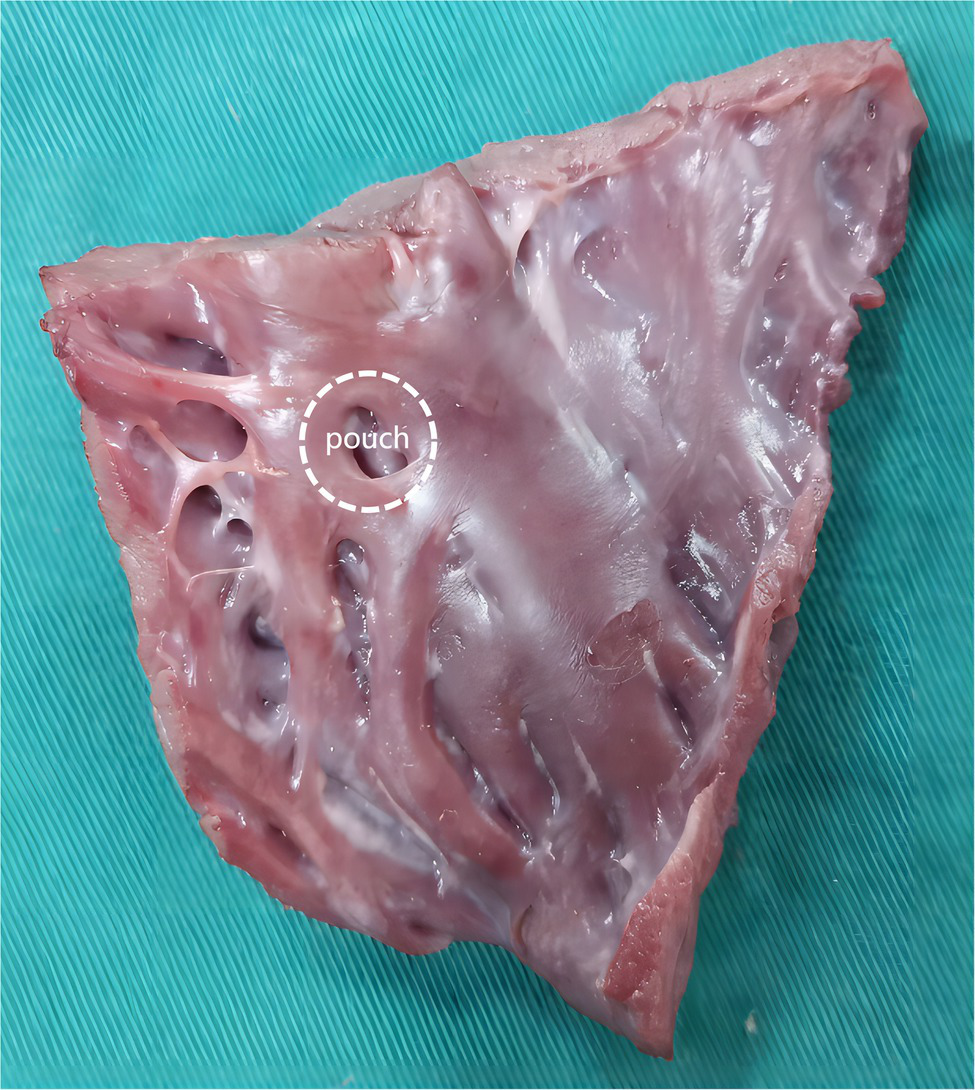

There are many pocket-shaped indentations of various sizes in the human endocardium, called pouches (Figure 1; Costa et al., 2004; Shimizu et al., 2018). Pouches can interfere with RFA, resulting in prolonged RFA duration (Chen et al., 2011; Shimizu et al., 2018). The sub-Eustachian pouch depth was independently associated with total RFA duration and radiofrequency energy delivered during cavotricuspid isthmus ablation (Shimizu et al., 2018). Some experts believe that resistive heating and impedance reduction at the beginning of RFA are associated with the amount of cardiac tissue surrounding the catheter tip (Viles-Gonzalez et al., 2017). When the catheter is placed in the pouch, its tip is surrounded by more cardiac tissue; therefore, a large amount of heat is rapidly generated. The rapid blood flow through the heart removes some of the heat, which is important to lower the temperatures of the catheter tip and cardiac tissue. However, blood flows slowly through the pouches. Therefore, theoretically, SP is more likely to occur in the pouches, but this assumption has not evaluated in previous studies.

Figure 1

A figure to show pouch.